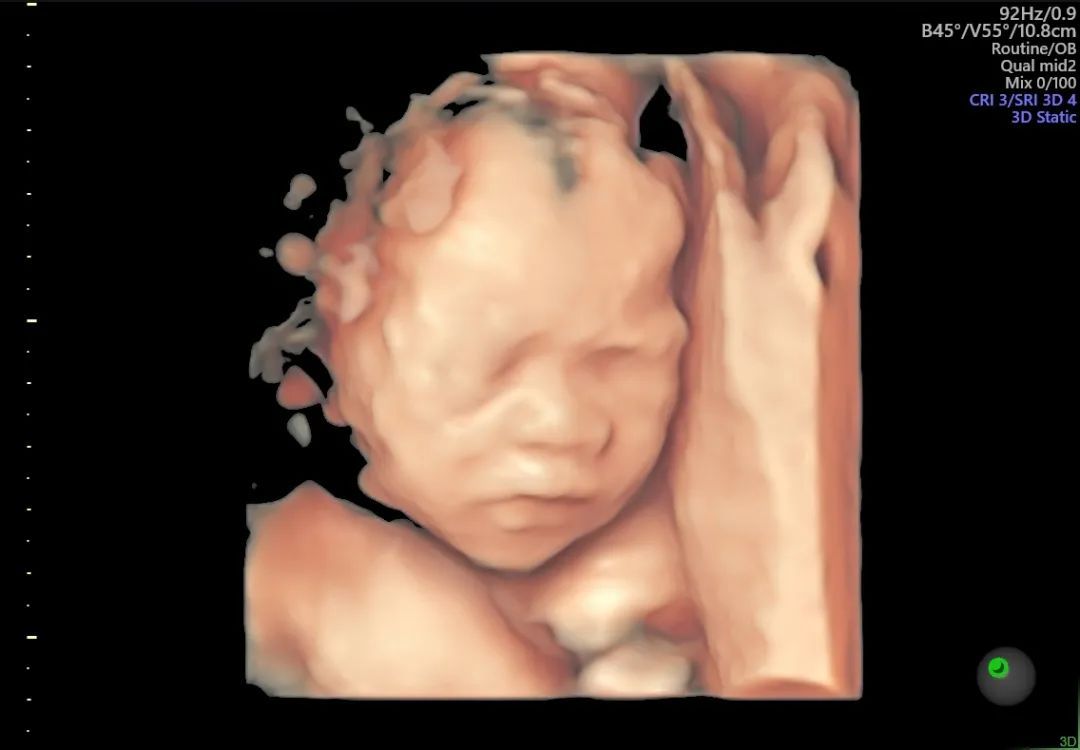

为满足不同孕妈的需求,GE- E10高清四维彩超仪采用了创新的煊光平台系统架构,更快的图像处理、更高的容积帧频提供了实时的结构信息及功能成像,刷新了妇产超声图像质量的新高度。

E10高清四维彩超没有射线、光波、电磁波等方面的辐射,对宝宝和孕妈的健康没有影响。E10设备能为早期诊断胎儿先天性体表畸形、心脏等畸形提供依据,同时新增6项排畸检测,排畸更智能!

▲图片为和平E10设备真实拍摄